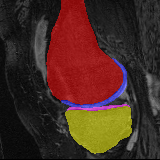

Moving

Target

Results: All trained networks are evaluated using Dice overlap scores between predictions and the manual segmentations for the segmentation network, or between the warped moving segmentations and the target segmentations for the registration network. Tabs. 1 and 2 show results for the knee and brain MRI experiments respectively in Dice scores (%). Fig. 2 shows examples of knee MRI registrations and brain MRI segmentations.

Qualitative results: DA achieves more anatomically consistent registrations than the mono-networks on the knee (Fig. 2) and Brain MRI samples (see supplementary material).